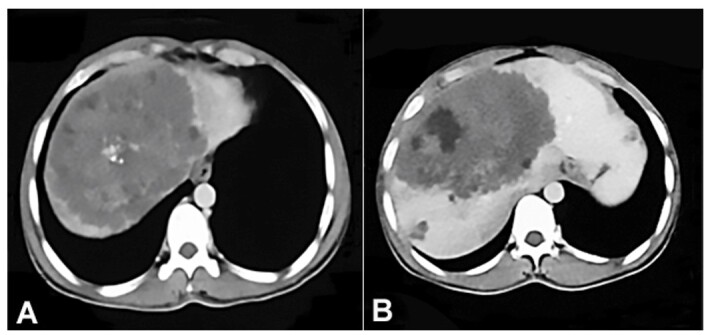

棘球蚴病是一种由棘球蚴属微小绦虫感染引起的寄生虫病。棘球蚴病分为囊性棘球蚴病和肺泡棘球蚴病两种。常见的是来自山羊和绵羊的人畜共患疾病,往往会引起肝脏病变。多形棘球蚴的幼虫阶段会导致肺泡棘球蚴病/肺泡水肿病。这是一种人畜共患病,田鼠和苔原田鼠是中间宿主,狐狸和狼等野生食肉动物是最终宿主。与另一种称为囊性棘球蚴病的疾病相比,这种人畜共患疾病并不常见,但如果不及时治疗,会对人类造成极大威胁。我们报告了一例在北印度克什米尔山谷工作的年轻男子的病例,他出现黄疸和右上腹疼痛。计算机断层扫描显示肝内有一个 125x118x123 毫米的巨大实性囊性病变,提示为恶性肿瘤,中央坏死。肝脏活检显示肝脏坏死并伴有PAS阳性膜,形态上与棘球蚴病一致。肺泡棘球蚴病可表现为肝脏中的实性囊性肿块,并可模拟转移性恶性肿瘤。

Echinococcosis is a parasitic disease caused by infection with tiny tapeworms of the genus Echinococcus. Echinococcosis is classified as either cystic echinococcosis or alveolar echinococcosis. The common form is a zoonosis from goats and sheep that tends to cause liver lesions. The larval stage of Echinococcus multilocularis causes alveolar echinococcosis/alveolar hydatid disease. It is a zoonosis with field mice and tundra voles as intermediate and wild carnivores like foxes and wolves as definitive hosts. This zoonosis is highly uncommon compared to the other form known as cystic echinococcosis but poses a great human threat if untreated. We report the case of a young man who was working in the Kashmir Valley, North India, and presented with jaundice and right upper quadrant abdominal pain. Computed tomography revealed a large solid-cystic intrahepatic lesion measuring 125x118x123 mm, suggestive of a malignant tumor with central necrosis. A liver biopsy showed necrosis with PAS-positive membranes morphologically consistent with echinococcosis. Alveolar echinococcosis can present as a solid-cystic mass in the liver and can simulate metastatic malignancy.